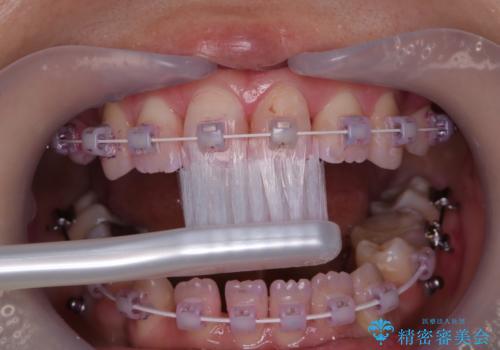

- ワイヤー矯正中のメンテナンスでPMTCを希望されました。染め出しを行い、歯ブラシ指導とPMTC30分コースを行いました。

毎日しっかりと磨いているようでも、装置の周りや歯と歯の間・歯と歯茎の間に磨き残しが残ってしまいます。そのため磨き残しをチェックする『染め出し剤』を使用すると明確に磨き残しを見ることができます。

この部分をしっかりと磨けるようになると、虫歯や歯周病を予防することができます。

矯正中にも、虫歯や歯周病予防をしっかり行うことが大切です。